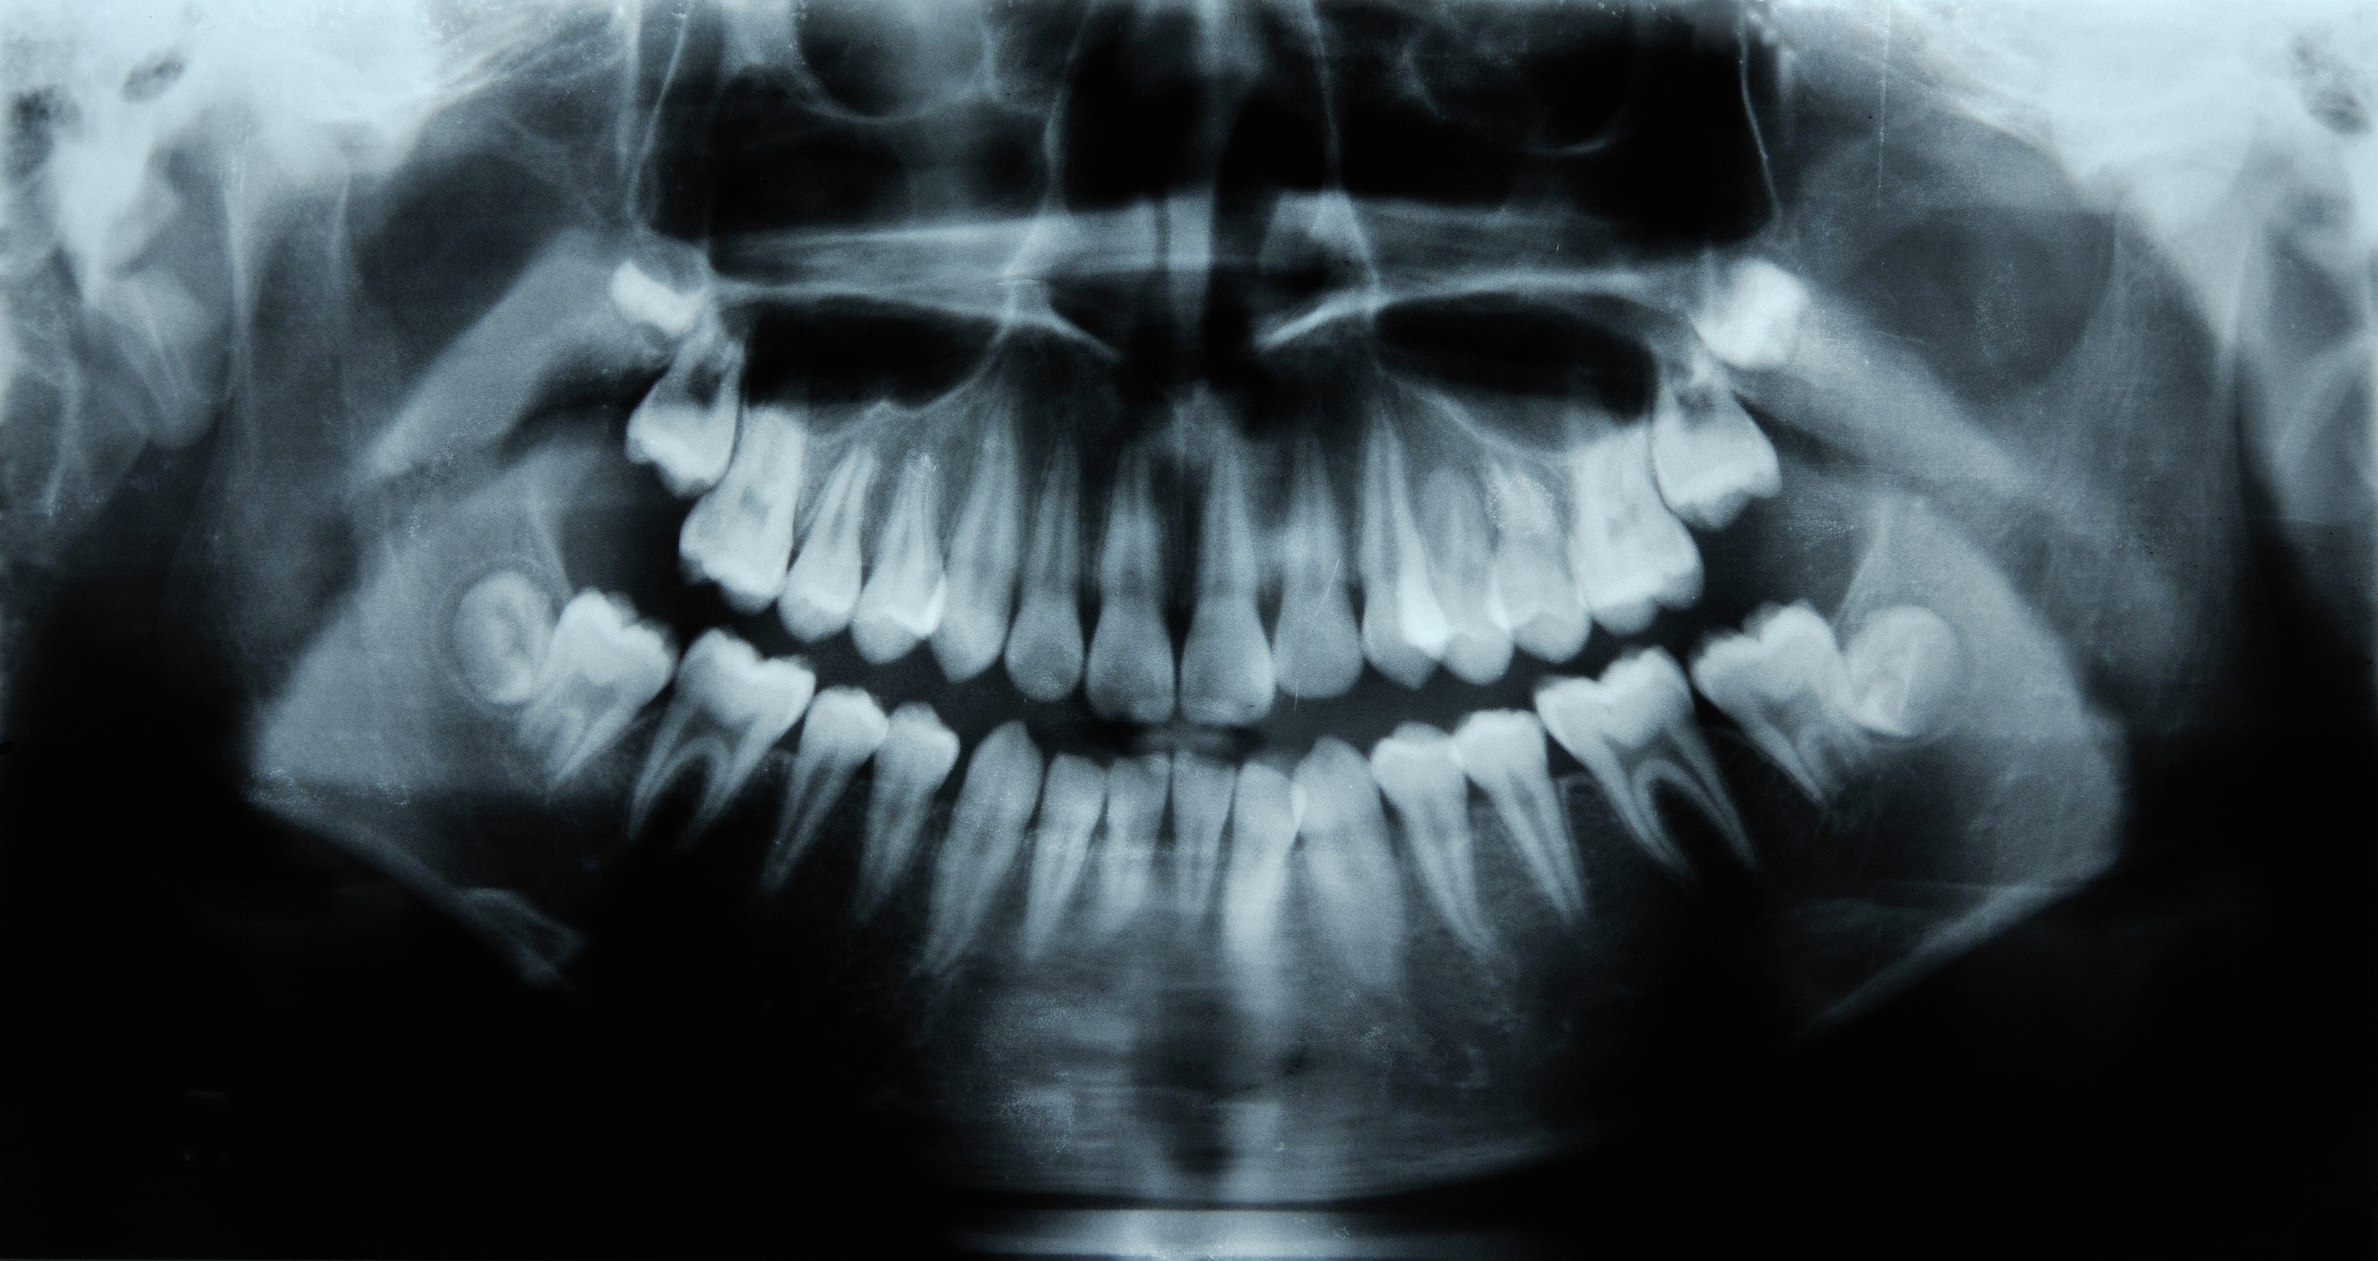

Tideglusib works by stimulating stem cells in the pulp of teeth, the source of new dentine. Dentine is the mineralized substance beneath tooth enamel that gets eaten away by tooth decay.

Teeth can naturally regenerate dentine without assistance, but only under certain circumstances. The pulp must be exposed through infection (such as decay) or trauma to prompt the manufacture of dentine. But even then, the tooth can only regrow a very thin layer naturally—not enough to repair cavities caused by decay, which are generally deep. Tideglusib changes this outcome because it turns off the GSK-3 enzyme, which stops dentine from forming.